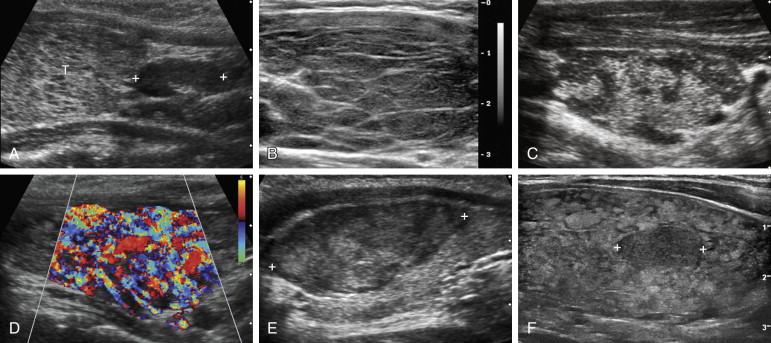

The basic underlying appearance of papillary cancer is a hypoechoic and entirely solid nodule ( Fig. 10-9 ). Approximately 15% to 20% of nodules with this appearance and no other findings will be malignant. Several additional findings make the likelihood of cancer even higher. Microcalcifications occur due to deposition of calcium salts in psammoma bodies and are common in papillary cancer. Although microcalcifications are uncommon in other thyroid nodules, crystals within colloid are common in nodular hyperplasia and can be confused with microcalcifications. Tumor growth that is greatest in the AP direction is occasionally seen with papillary cancer and leads to a taller-than-wide configuration. This appearance is very uncommon with benign nodules. A lobulated margin is another feature that further increases the risk of cancer. The lobulations may be large or small. A solid, hypoechoic nodule that contains one or more of these additional malignant features mentioned earlier has a 50% to 80% risk of being cancer. Other findings that are seen less frequently with papillary cancer are peripheral calcifications (usually dis­continuous), coarse-shadowing calcifications, and refractive shadowing.

F igure 10-9, Papillary thyroid cancer (cursors) in different patients. A, Transverse view shows a 9-mm homogeneous, hypoechoic, entirely solid lesion. B, Longitudinal view shows a 7-mm homogeneous, hypoechoic, solid lesion that contains scattered microcalcifications. C, Longitudinal view shows a 43-mm solid, hypoechoic lesion with scattered microcalcifications. D, Longitudinal view shows a solid, hypoechoic lesion with lobulated margins. E, Longitudinal view shows a solid, hypoechoic nodule that is taller than wide. F, Transverse view shows a solid, hypoechoic nodule that is taller than wide and bulges the anterior capsule. G, Longitudinal view shows a solid, hypoechoic nodule with a discontinuous rim of calcification. H, Longitudinal view shows a 21-mm solid, hypoechoic nodule with coarse calcification. I, Longitudinal view shows a solid, hypoechoic nodule with refractive shadowing at both edges.

A minority of papillary cancers have substantial cystic components and overlap in appearance with benign nodular hyperplasia ( Fig. 10-10 ). For this reason most guidelines for performing FNA recommend FNA for nodules larger than 2 cm even if they have benign sonographic features.

F igure 10-10, Cystic papillary cancer (cursors) in different patients. A, Longitudinal view shows a predominantly cystic nodule with septations and minimal solid elements. B, Longitudinal view shows a subcentimeter mixed solid and cystic nodule.